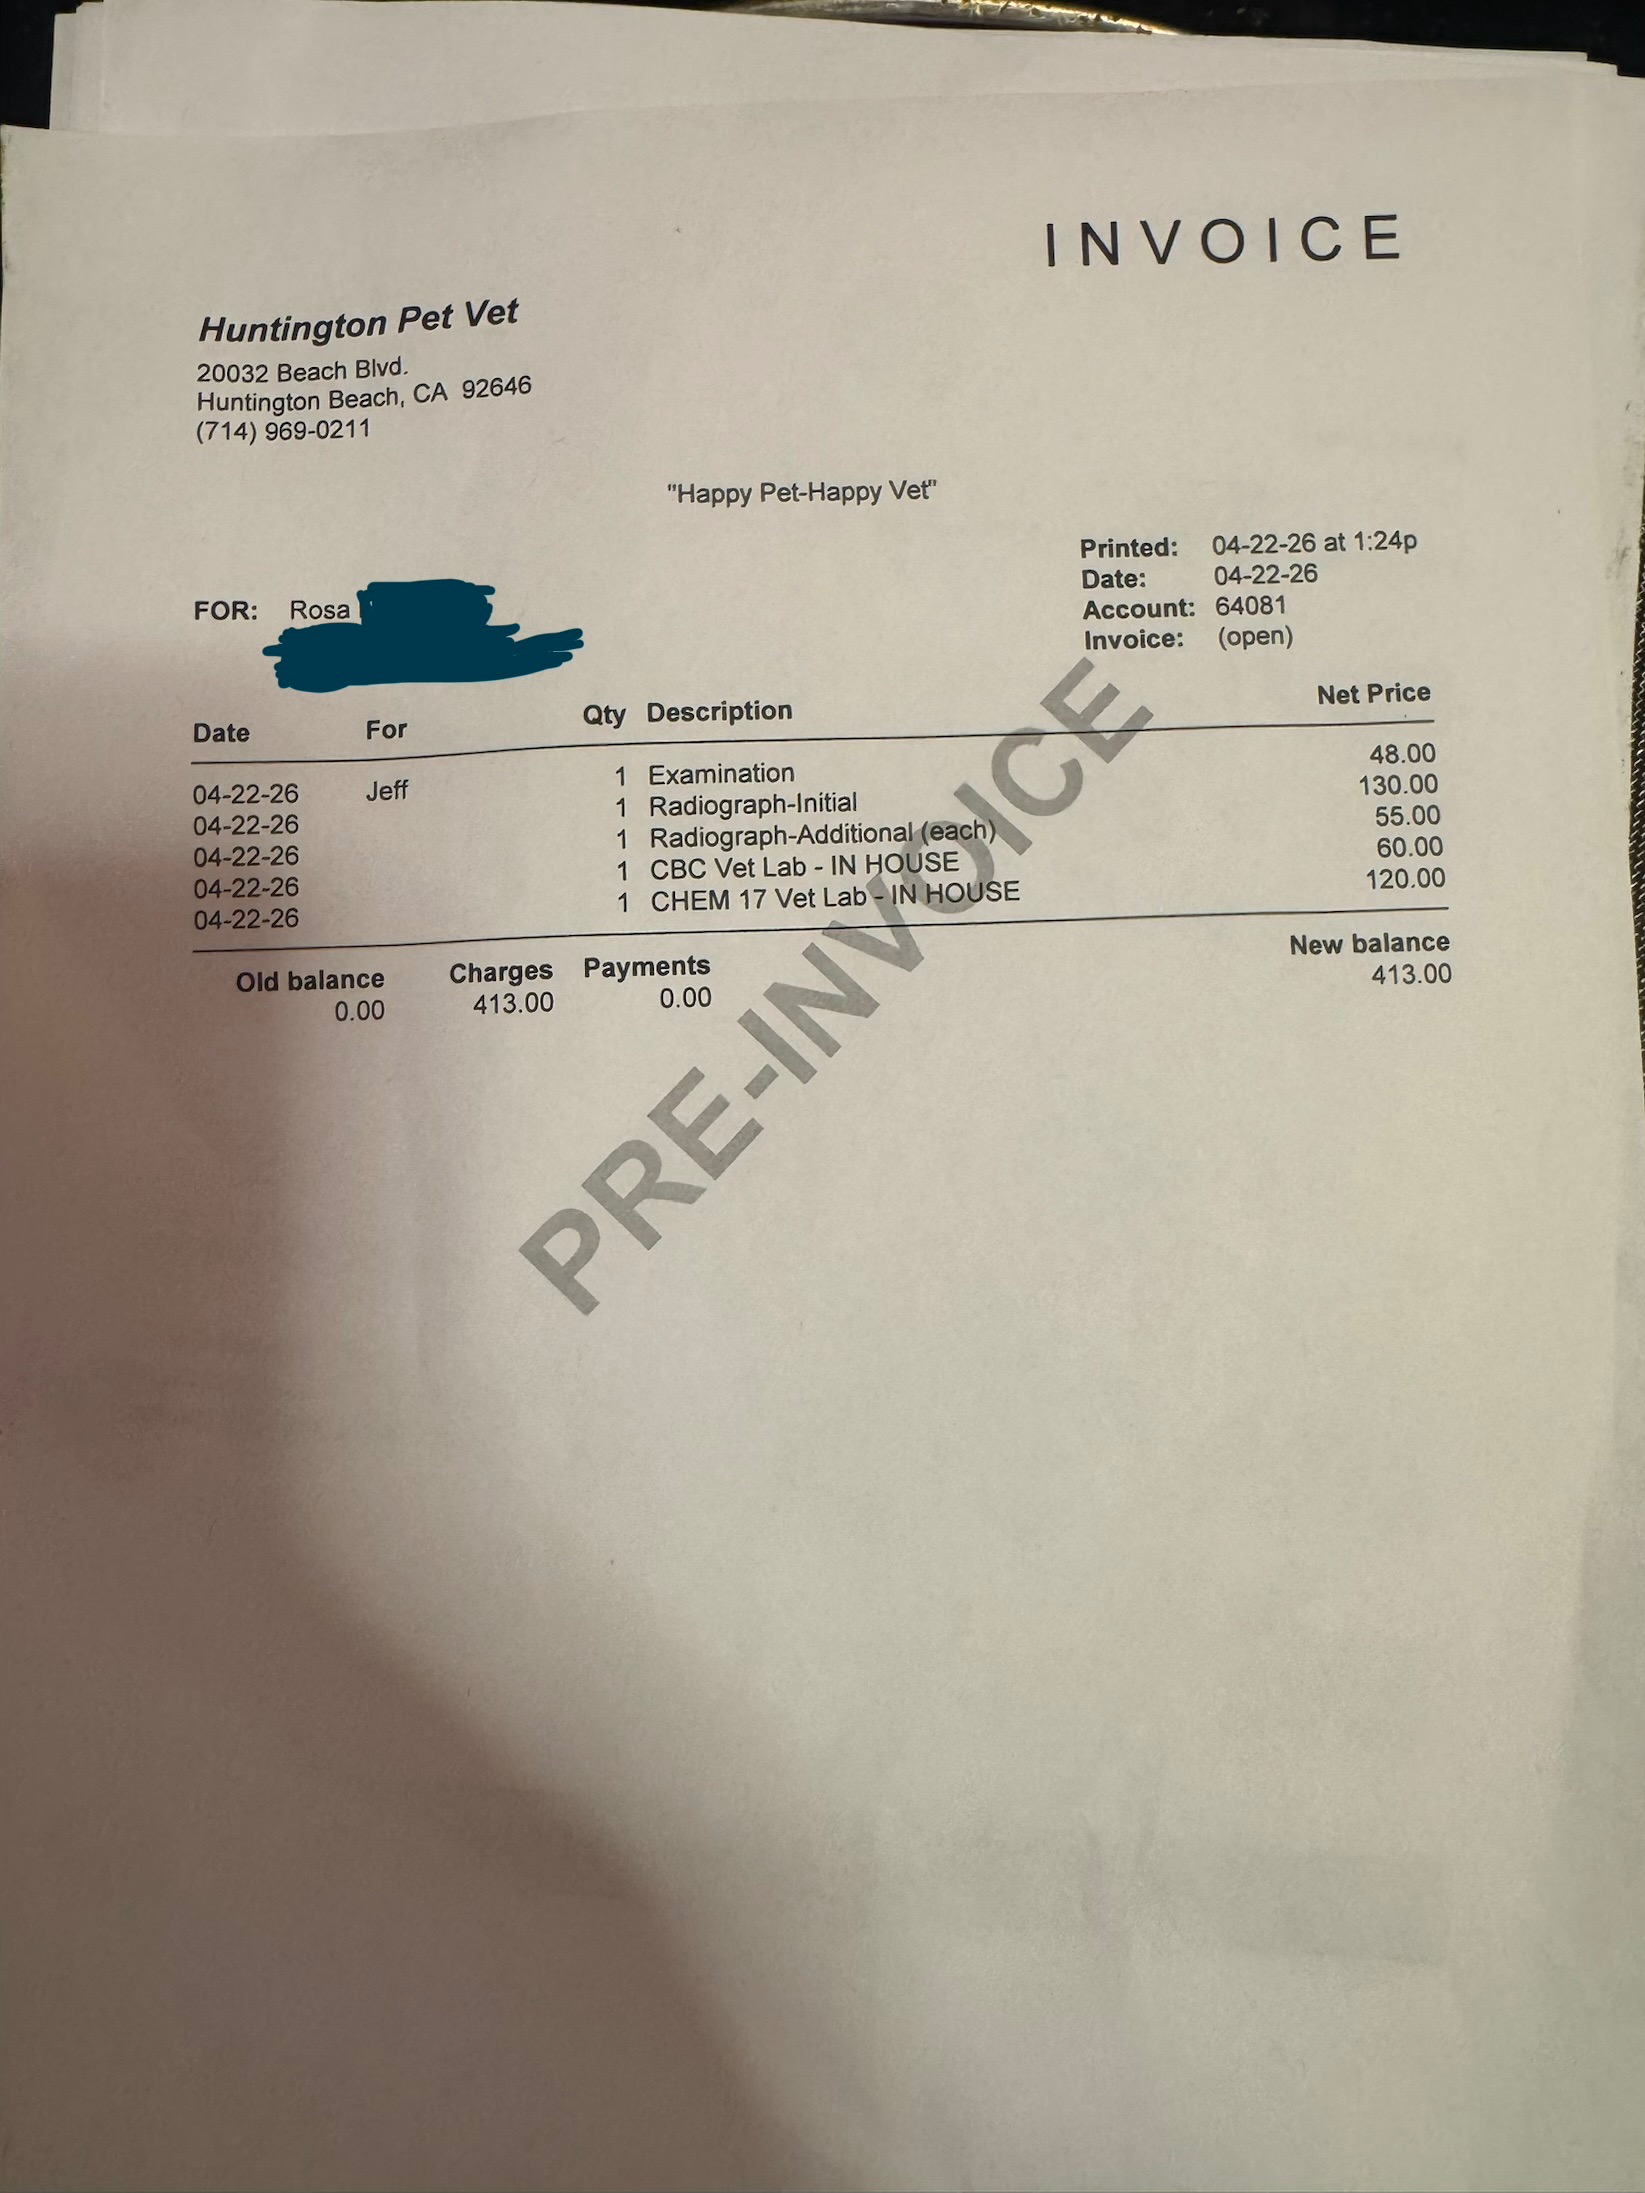

We rushed Jeff to the vet, where he is now being cared for and will need to stay for three days. At first, we thought he might have been hit by a car, but the x-rays revealed something even more heartbreaking—Jeff had been shot. I was able to get approved for CareCredit, but only for a limited amount, and the costs of his care are far beyond what I can cover alone. Jeff will need surgery after observation, depending on his condition, and the emotional toll on my daughter and me has been overwhelming. We can’t understand why someone would do this to such a sweet, loving animal.

I am reaching out to ask for help from anyone who can find it in their hearts to support Jeff’s recovery. I truly hate to ask, but I have to—for Jeff, for my daughter, and for our family. Anything you can contribute will help us give Jeff the care he needs to survive and heal. As an animal lover, I know how much our pets mean to us, and Jeff is so much more than just a cat—he is family. Thank you for considering helping us in this difficult time. I will attach documentation from today’s vet visit.